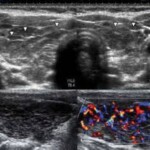

Ἡ διάγνωση τίθεται κυρίως ἐργαστηριακά. Τὸ ὑπερηχογράφημα δείχνει ἀνομοιογενῶς ὑπόηχη παρεγχυματικὴ ὑφή καὶ πλούσια ἀγγείωση. Στὰ μικροβιολογικὰ περιμένουμε αὔξηση τῆς TSH (ὑποθυρεοειδισμός) καὶ τῶν ἀντισωμάτων (Anti-Tg, anti TPO).